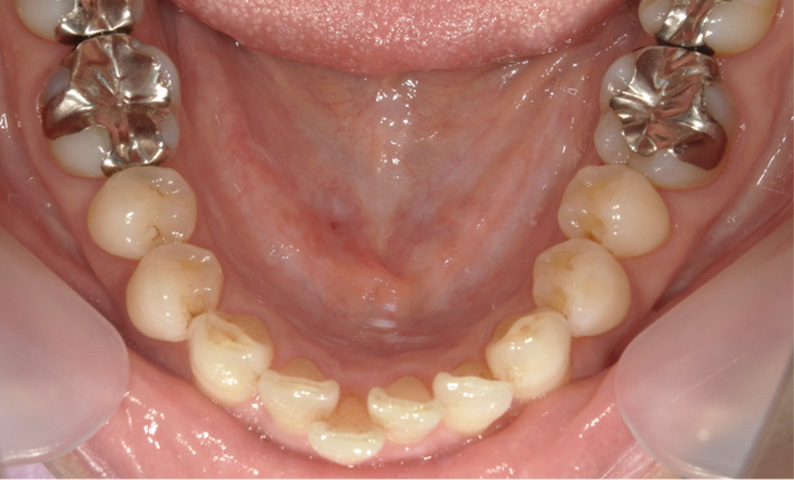

症例_005 「出っ歯」症例

治療期間:12ヶ月金額:54万円+税20代女性出っ歯八重歯捻転歯